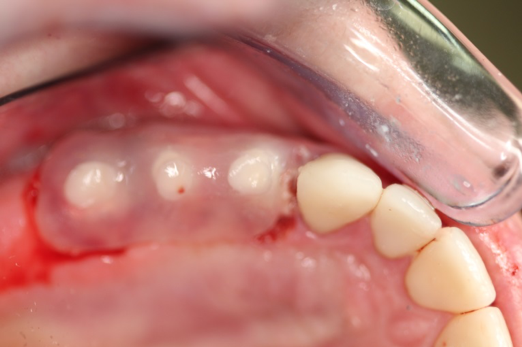

Fig 12. Ceramic implants placed and sutured.

Figure 12

Figure 10 through Figure 13 show the preoperative x-ray and the sequence of beginning with healed sites through the surgical placement of the implants. The implants were protected by an Essix-style wound-protection removable retainer for approximately 12 weeks. After the integration phase, the implants and the natural dentition were prepared using traditional crown-and-bridge high-speed diamond and zirconia cutting burs to remove decay and existing restorative materials, to complete and refine the natural-tooth structures to receive full-crown coverage, and to prepare and refine gingival margins of the zirconia implants where needed.